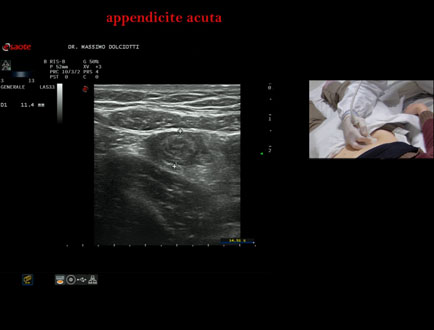

Data inserimento: 15/01/2026

Ecografia del: 07/01/2025

Strumento: Esaote MyLab Eight

Sonda: Lineare Multifrequenza 3-13 MHz

Età Paziente: F 39 anni

Motivazione dell'esame: dolori addominali epiastrici da 2 gg, anche notturni, non nausea, non vomito, non diarrea, non febbre, diuresi normale, nicturia saltuariamente.

Commento all'esame: le immagini ed il video documentano, in sede ileo-cecale, appendice di spessore aumentato (11 mm - V.N. inferiore a 6 mm). Gli elementi ecografici segnalati orientano per appendicite acuta.

Conclusioni: appendicite acuta (acute appendicitis).

In collaborazione: Dr.ssa Marica Manfredi - Ancona, Dr. Ilir Qose - Ancona

Presentazione: Dr. Massimo Dolciotti - Ancona

Elaborazione digitale: Andrea Dini - Ancona